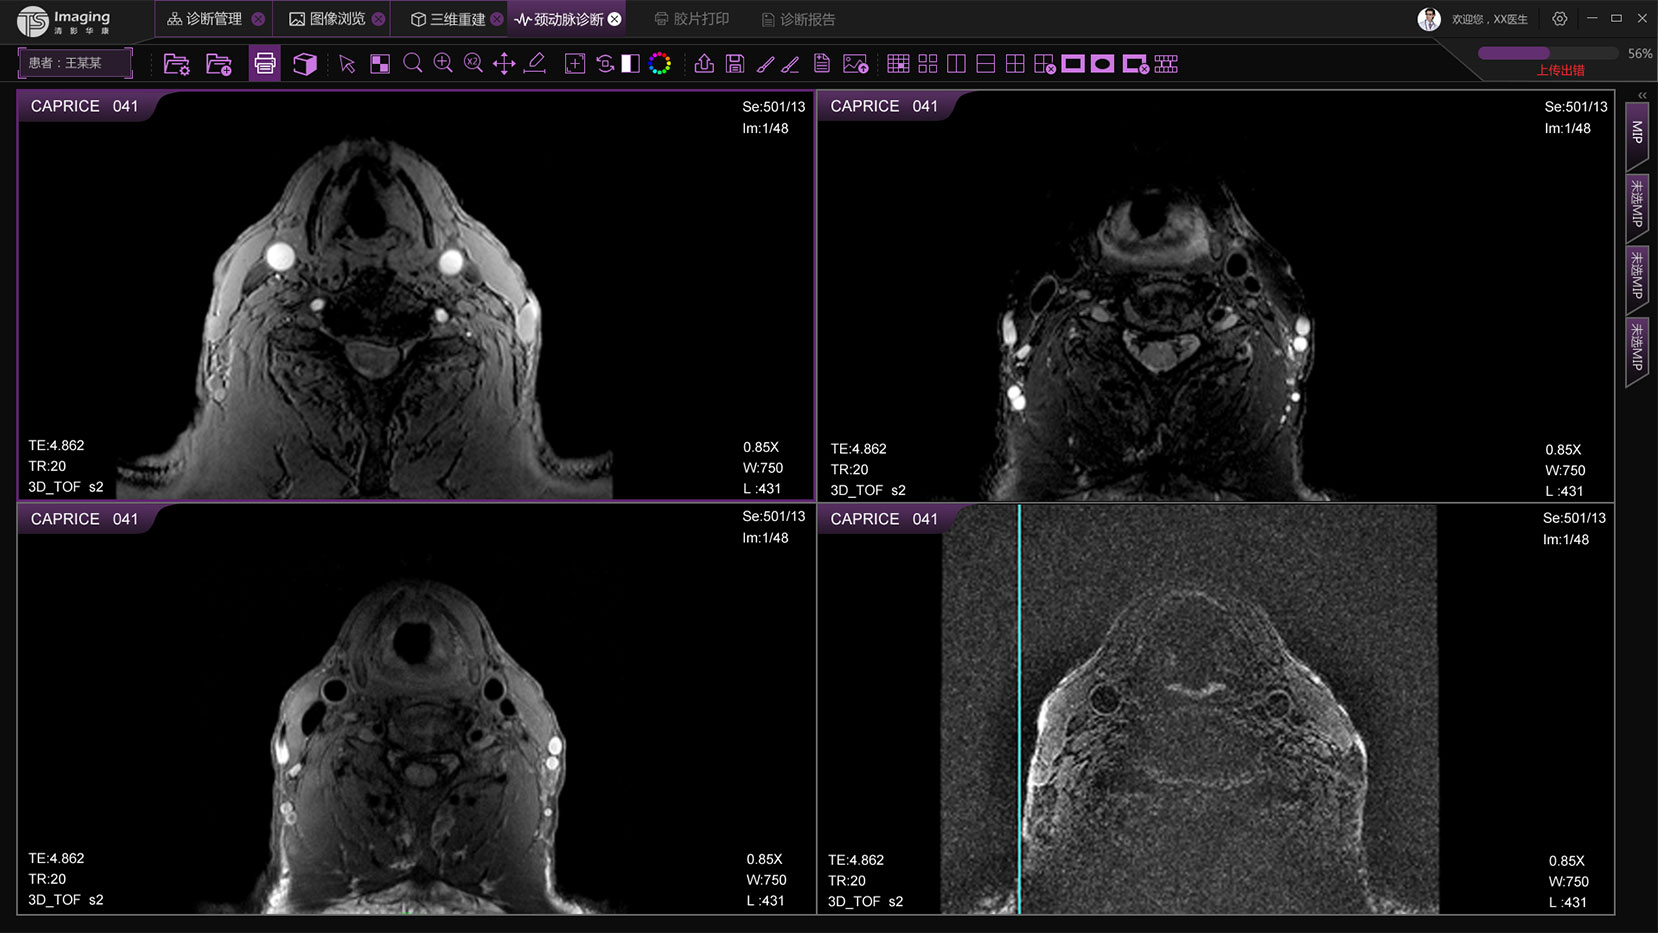

頸動脈診斷頁面

頸動脈診斷頁面整體布局和三維重建比較相似,最大的區別是右側的操作區域,血管分析都為按鍵操作,通過間隔的大小分成三部分。單層切片除了按鍵還有下拉菜單的操作。